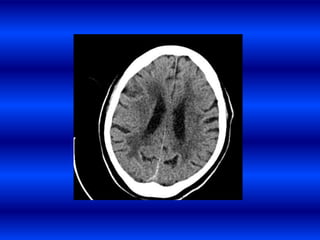

Infarto cerebral silente.

• Una gran parte de los enfermos tienen

dificultades cognitivas, de la marcha u otros

síntomas que por ser ligeros pueden no

reconocerse

INFARTOS SUBCLÍNICOS

Los estudios poblacionales han demostrado que los infartos subclínicos

incrementan 2-4 veces el riesgo de infarto clínico

• Estudios poblacionales usando RMN han

demostrado que el 8-28 % de los adultos

tienen evidencias de infartos silentes.

• Imagen hipointensa en T1 3 mm.

• Si se suman los infartos silentes a los

infartos clínicos, la prevalencia de ECV se

incrementa a aproximadamente 20 % de la

población.

• 23.

Infarto cerebral silente. •Una gran parte de los enfermos tienen dificultades cognitivas, de la marcha u otros síntomas que por ser ligeros pueden no reconocerse INFARTOS SUBCLÍNICOS Los estudios poblacionales han demostrado que los infartos subclínicos incrementan 2-4 veces el riesgo de infarto clínico

• 24.

• Estudios poblacionalesusando RMN han demostrado que el 8-28 % de los adultos tienen evidencias de infartos silentes. • Imagen hipointensa en T1 3 mm. • Si se suman los infartos silentes a los infartos clínicos, la prevalencia de ECV se incrementa a aproximadamente 20 % de la población.